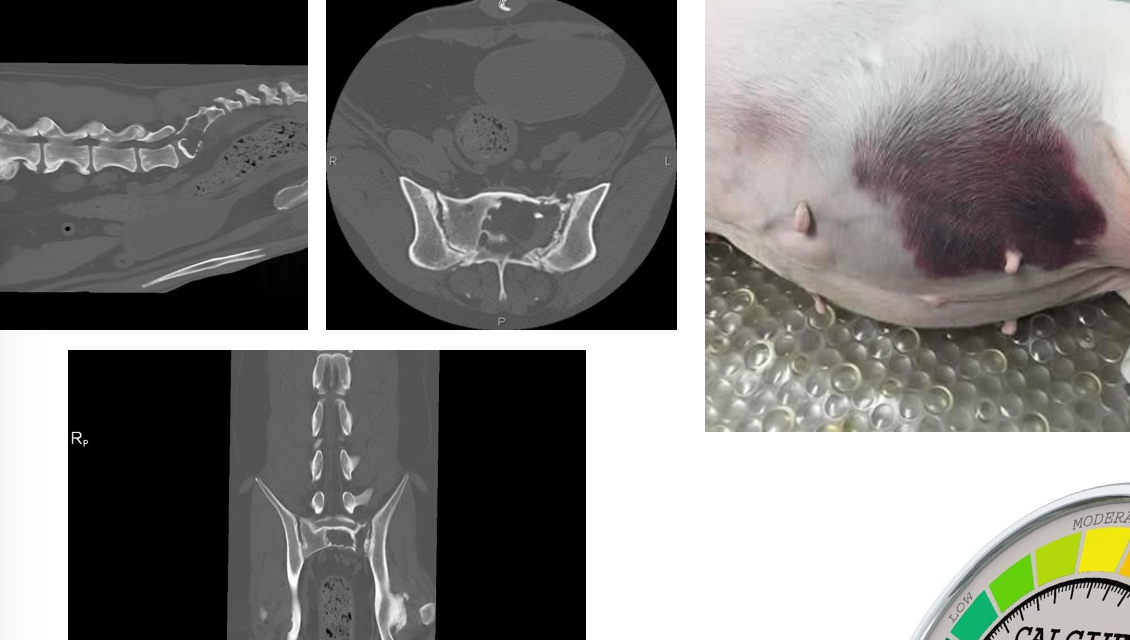

How can radiographic bone lesions appear?

Can be isolated, discrete lesions or diffuse osteopenia

Common sites have active hematopoiesis → vertebrae, ribs, skull, proximal and distal long bones

radiographic bone lesions

2. lytic bone lesions

what diagnostic tests for multiple myeloma are used to assess extent of disease?

imaging:

-thorax (rads/CT)

-abdomen (rads, US, CT- especially in cats since they tend to have the visceral form)

-skeleton (CT, rads)